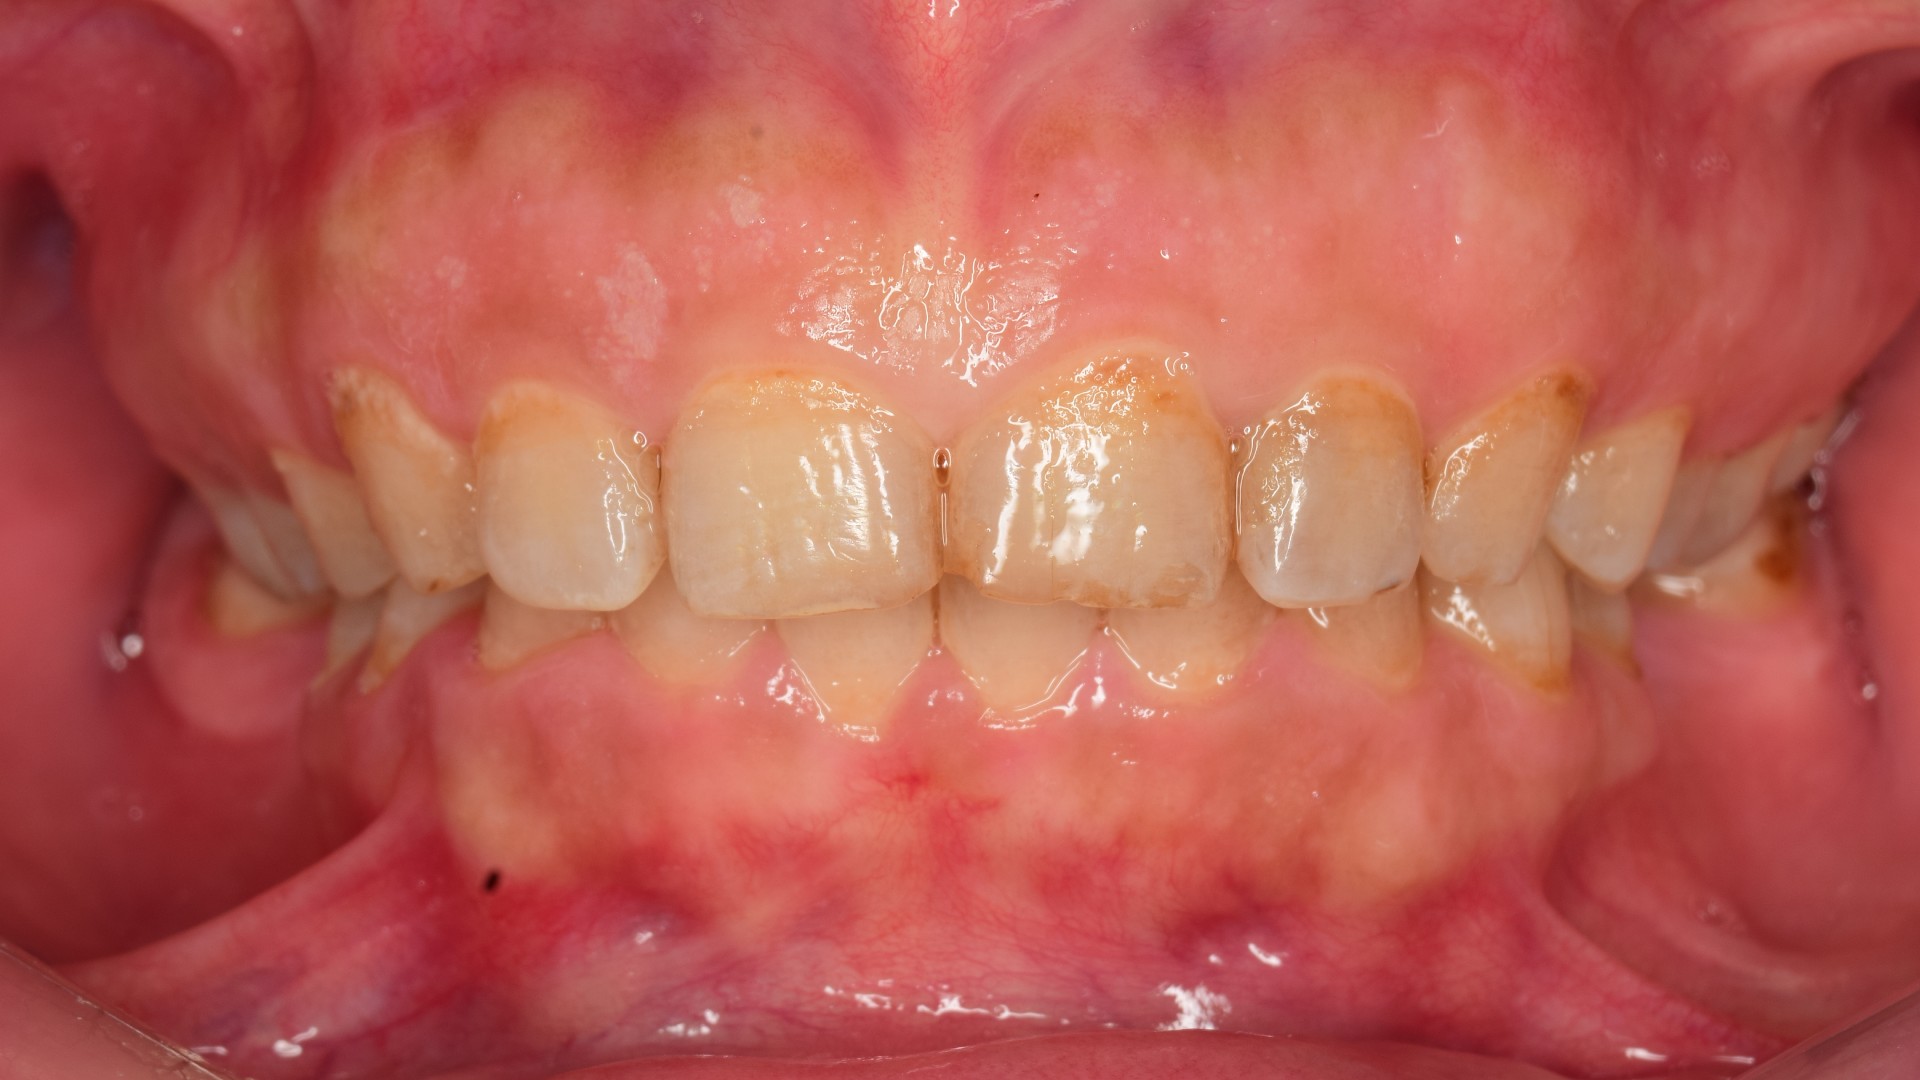

Closing the gap Picture

By Dr.Ali AlaaAdded on December 2025

Closing the gap

or should I say reclosing the gap?

Patient presented with pre-existing composite restorations closing the spaces between the incisor teeth. However, Patient complained that a piece of t...

Read More